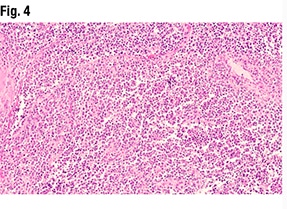

Another part of the tumor (Fig. 3) did show glandular formations, she said, noting that scattered throughout the image are glandular lumens filled with eosinophilic secretions. “The glands themselves are close to pseudostratified in appearance—variable size in the nuclei but not wildly pleomorphic,” she said, and without significant mitotic activity. “Very back-to-back, not seeing very much intervening stroma. So based on this morphology it looks like an endometrioid tumor that is pretty much all gland forming.” But in other areas (Fig. 4), “we see much more solid morphology—it’s not forming glands, it’s not forming papillary structures, it’s very monotonous in appearance,” and it has a high nucleus-to-cytoplasmic ratio. “We do get a sense that there’s mitotic activity,” she said. “So very high grade, very solid. This is not forming any glands at all.”